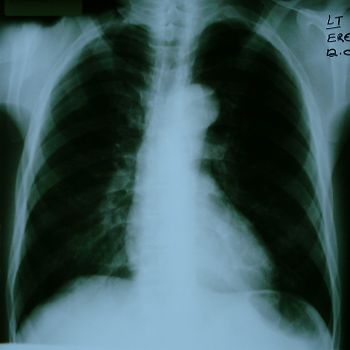

A forty six year old black male was admitted with ischaemic lower limbs. He had overt gangrene of the left foot with rest pain. History was difficult to obtain, but on direct questioning he had a vague history of ill-defined chest pain. He appeared ill and toxic, was pyrexial, and the left foot smelled grossly offensive. All his lower limb pulses were absent. The rest of his examination (including cardiac examination) was non-contributory. He had no risk factors for cardiovascular disease apart from a thirty pack-year smoking history. Baseline investigations showed a moderate leukocytosis and mild hyponatraemia (Serum sodium 129 mmol/l) but no other abnormalities. His chest x-ray is shown in figure 1.

Chest x-ray of patient showing a normal-sized heart, really rather unremarkable but is there pulmonary oedema?

Fig 1. The patient's chest x-ray

QUESTION 1. In view of the chest x-ray, does the MUGA ejection fraction surprise you?